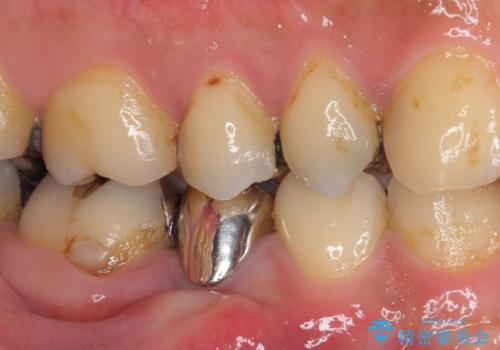

当初は根管治療を再度行うことで痛みが引くことを期待しましたが、該当歯の歯周ポケットが局所的に深くなっていることから、歯に穴が開けられているか破折している可能性が疑われました。

歯肉を開いたところ、周辺の歯槽骨は全て炎症で失われ、破折と同等の穴が開けられていることが分かったため、抜歯を行いフルジルコニアブリッジにて補綴することとしました。